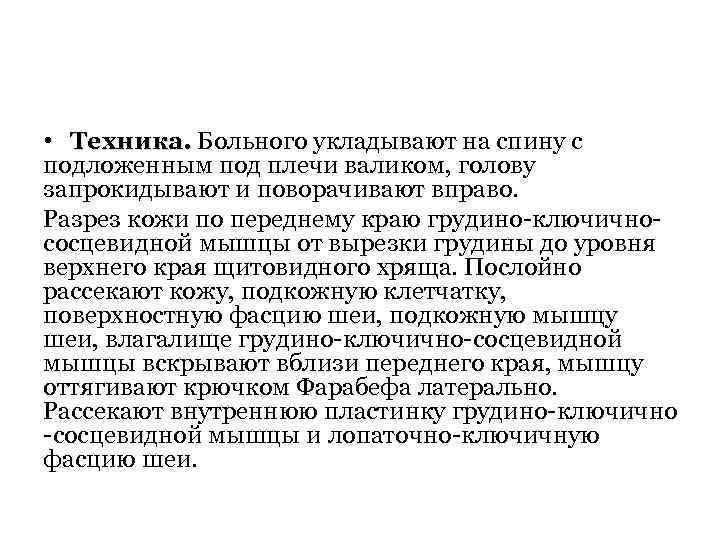

• Техника. Больного укладывают на спину с подложенным под плечи валиком, голову запрокидывают и поворачивают вправо. Разрез кожи по переднему краю грудино-ключичнососцевидной мышцы от вырезки грудины до уровня верхнего края щитовидного хряща. Послойно рассекают кожу, подкожную клетчатку, поверхностную фасцию шеи, подкожную мышцу шеи, влагалище грудино-ключично-сосцевидной мышцы вскрывают вблизи переднего края, мышцу оттягивают крючком Фарабефа латерально. Рассекают внутреннюю пластинку грудино-ключично -сосцевидной мышцы и лопаточно-ключичную фасцию шеи.

• Техника. Больного укладывают на спину с подложенным под плечи валиком, голову запрокидывают и поворачивают вправо. Разрез кожи по переднему краю грудино-ключичнососцевидной мышцы от вырезки грудины до уровня верхнего края щитовидного хряща. Послойно рассекают кожу, подкожную клетчатку, поверхностную фасцию шеи, подкожную мышцу шеи, влагалище грудино-ключично-сосцевидной мышцы вскрывают вблизи переднего края, мышцу оттягивают крючком Фарабефа латерально. Рассекают внутреннюю пластинку грудино-ключично -сосцевидной мышцы и лопаточно-ключичную фасцию шеи.

• Левую долю щитовидной железы вместе с трахеей и мышцами (грудино-подъязычной, грудинощитовидной) оттягивают и отодвигают кверху и вправо. Перевязывают нижнюю щитовидную артерию, отодвигают кверху лопаточно-подъязычную мышцу (при короткой шее её пересекают). Разъдиняют тупым способом листок внутришейной фасции, обнажают клетчатку пищеводно-трахейной борозды, где проходит левый возвратный гортанный нерв. Стенку пищевода определяют по красному цвету и продольной исчерченности.

• Левую долю щитовидной железы вместе с трахеей и мышцами (грудино-подъязычной, грудинощитовидной) оттягивают и отодвигают кверху и вправо. Перевязывают нижнюю щитовидную артерию, отодвигают кверху лопаточно-подъязычную мышцу (при короткой шее её пересекают). Разъдиняют тупым способом листок внутришейной фасции, обнажают клетчатку пищеводно-трахейной борозды, где проходит левый возвратный гортанный нерв. Стенку пищевода определяют по красному цвету и продольной исчерченности.